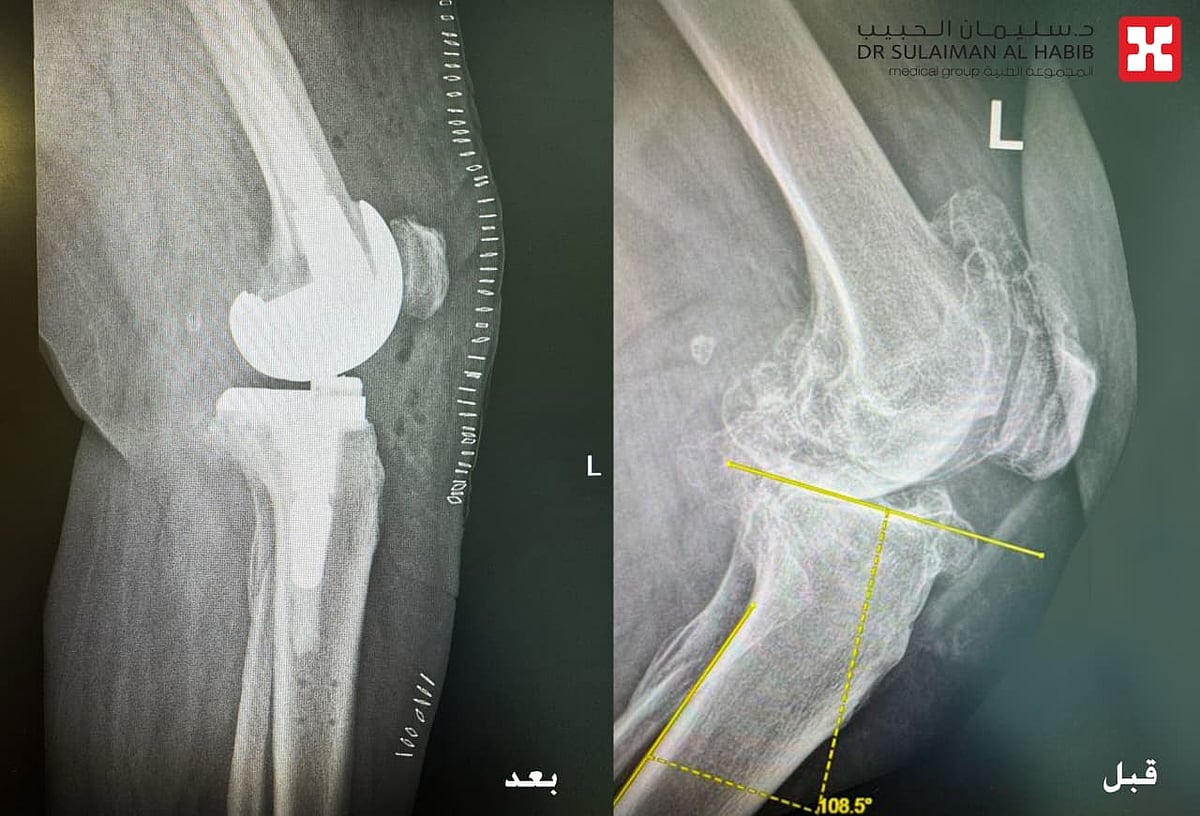

نجح مستشفى الدكتور سليمان الحبيب بالخبر، وعبر تقنية الروبوت الجراحي “Robotic Surgery”، في إنهاء معاناة مراجعة تبلغ من العمر 84 سنة، كانت تشكو من ألم حاد ومزمن في مفصل الركبة اليسرى، أفقدها القدرة على المشي. ذكر ذلك الدكتور محمد سكيك استشاري طب وجراحة العظام واستبدال المفاصل، رئيس الفريق الطبي المعالج الحاصل على الزمالة البريطانية والكندية.